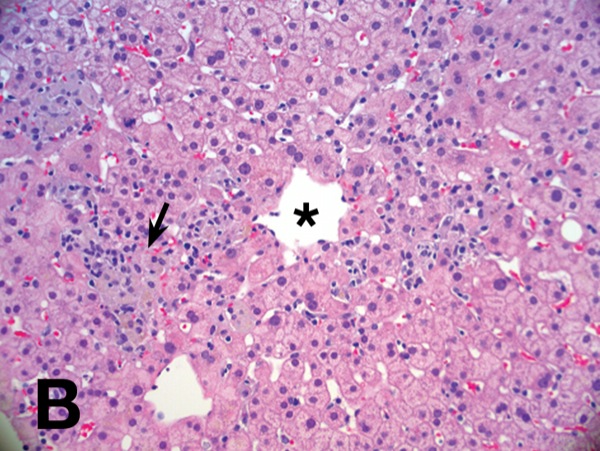

Ceroid Laden Macrophages Liver. Elucidating the mechanisms by which they mediate this process is crucial. Venous outflow obstruction Other Changes Seen in Areas of Severe Parenchymal Necrosis Congestion. Figure 1610 Ceroid laden macrophages. There are numerous ceroid-laden macrophages throughout consistent with prior injury.